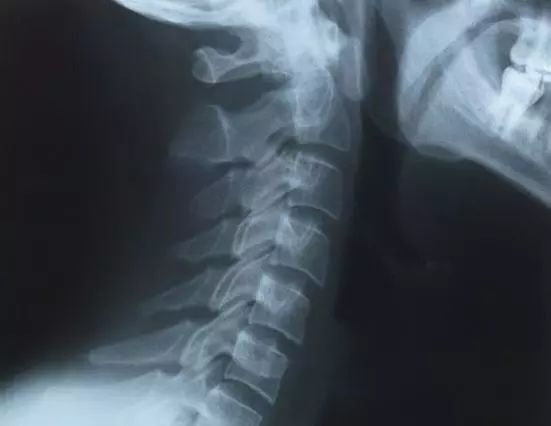

颈椎退行性变是指颈椎结构的衰变及机能的衰退。年龄增长以及与之相关的使用过度、修复能力降低是引起颈椎退变的主要原因。颈椎退变本身不是疾病,有时甚至是机体对于环境的适应性改变;颈椎退变不可避免,是每个人都会经历的生命过程,然而某些情况下会成为颈椎病等退行性疾病的发病基础,是造成颈脊髓、神经根等重要结构损害的主要原因。正确认识颈椎退变、减缓退变进程以及避免其发展为疾病是十分重要的。

人类的颈椎由7节椎体以及之间的小关节、椎间盘、纵向连接的韧带(从前至后依次为前纵韧带、后纵韧带、黄韧带、棘间韧带、棘上韧带,颈段的棘上韧带又称为项韧带)、椎旁的肌肉、筋膜等软组织构成。其中第1、2节颈椎分别称为寰椎、枢椎,其形态特点、连接结构以及功能与其他5节不同,称为上颈椎。与之对应,第3~7节称为下颈椎。由于上颈椎容纳脊髓的空间——椎管相对宽大,加之第1、2颈椎间没有椎间盘结构,所以脊髓等重要结构较少在此受到压迫,发病率远低于下颈椎。在上颈椎水平,造成脊髓损害的原因也与下颈椎不同,主要是由颈1、2节之间的不稳定或脱位引起,退变造成的局部韧带(寰椎横韧带为主)松弛是其重要原因。

此外,颅、颈交界区易发生先天畸形,这使局部应力增加,退变加速,增加了进展为疾病的风险。下颈椎最早发生退变的结构是椎间盘,椎间关节、韧带等结构继之发生退变,当这些退变造成颈脊髓、神经、血管等重要结构损害并出现相应的临床表现时,即从单纯的颈椎退变进展为疾病。下面着重讲述颈椎的主要结构及其相应的退行性改变的特点,尽管也介绍这些退变与疾病的内在联系,但并不意味着退变必然会引起疾病。

1、椎体骨赘形成

骨赘俗称骨刺,易出现于椎体的上下端的前缘、后缘及神经通道周围。骨赘的形成通常认为是由于椎间盘退变后高度降低,纤维环向四周膨隆,使周围的韧带受到张力而牵拉骨膜,刺激新骨形成,即所谓的“牵张性骨赘”;

椎间盘高度降低亦造成椎体前、后纵韧带松弛,椎体稳定性下降,增加了椎体间的异常活动,从而容易发生反复的、微小的创伤,创伤出血后血肿经过机化、骨化等成骨过程,即在此形成骨赘。骨赘形成后机械性阻碍了椎体间的活动,甚至由于相邻椎体间骨赘的连接而完全丧失椎间活动,从而相对的增加了其稳定性,这种改变可视为一种对机体有利的代偿,在牺牲了部分运动能力的情况下尽量保持椎间的稳定,避免椎体间的过度活动造成脊髓等重要组织的损伤。然而,神经周围的骨赘无疑会占据容纳神经组织的空间,过度生长的骨赘连同膨出的纤维环、后纵韧带和创伤反应所引起的水肿或纤维化组织形成突向椎管的混合突出物,会造成神经受压,椎管本就狭窄的个体(如发育性颈椎管狭窄,国人标准为椎管中矢状径与椎体中矢状径比值小于0.75)出现这一问题的风险更高。

骨端骨赘的形成是一个缓慢的过程,造成的损害通常也是逐渐发生的,由于机体对于缓慢发生的压迫具有较强的耐受能力,所以往往在出现临床症状之前数月甚至数年就已经存在神经受压。椎体前缘的骨赘由于远离神经结构,所以大多不会引起症状,但当骨赘巨大造成椎体前方软组织受到挤压时,则可能出现吞咽困难、声音嘶哑等症状。

2、关节突关节、钩椎关节以及韧带结构的退变

颈椎体间的连接除了椎间盘之外,还有两侧的关节突关节、钩椎关节以及纵行的韧带结构。这些结构在椎间不稳定时负荷增加,出现过度活动,易于出现关节的骨质增生,关节间隙变窄,神经通道处的骨赘可造成神经卡压;韧带出现肥厚、钙化或者骨化,尤其是后纵韧带、黄韧带这些骨性椎管内的韧带,在颈椎活动时肥厚的韧带易于褶皱变形,突向脊髓,使脊髓周围的有效间隙减小,甚至造成脊髓压迫。项韧带在颈椎不稳定的节段容易出现累积性创伤而产生软骨化和骨化。